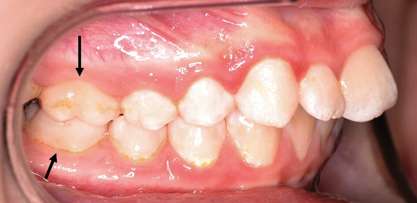

Fig 3. Impacted canine, dentofacial signs.

Figure 3

Dental impactions may occur for several reasons. A common occurrence is insufficient arch length leading to crowding. Another potential reason is early loss of primary teeth without proper space maintenance, allowing the permanent dentition to drift mesially and block out the primary tooth's successor. Maxillary canines are the most commonly impacted teeth besides third molars. These teeth have the longest path of eruption, are one of the last teeth to erupt into the mouth, easily become blocked out due to crowding or trauma history, and have a genetic component to being palatally impacted.5,6 Early signs of canine impaction may be severe crowding and the permanent lateral incisor crowns flaring distally. The crown of the impacted canine, in essence, is applying pressure to the roots of the lateral incisors in these instances (Figure 3 and Figure 4).